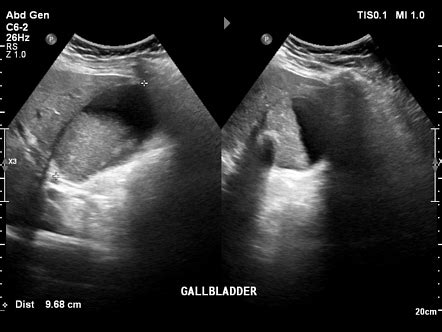

The condition can result from. Web cholelithiasis is the medical name for gallstones — hard deposits of cholesterol or bilirubin that form in the gallbladder. Mucocele or hydrops of the gallbladder is defined as an overdistended gallbladder filled with mucoid or clear and watery content. Web mucocele of the gallbladder is a condition caused by the prolonged blockage of the cystic duct, usually by an impacted gallstone. Hydrops fetalis… see the full definition. A large calculus in the neck of the gallbladder. The condition can result from. Another name for this condition is. Web gallbladder hydrops, also known as hydropic gallbladder or mucocele of the gallbladder, occurs secondary to obstruction of the cystic duct, often by a gallstone. Web hydrops of the gallbladder is an uncommon condition of infants and children.

Hydrops fetalis… see the full definition. Web gallbladder sludge can cause or contribute to cholecystitis, which is an inflamed gallbladder. Your gallbladder stores and releases bile to help your digestive system break down fats. Web the meaning of hydrops is edema. How to use hydrops in a sentence. A large calculus in the neck of the gallbladder. The distinction between acalculous cholecystitis and hydrops is therefore one of histology. Mucocele or hydrops of the gallbladder is defined as an overdistended gallbladder filled with mucoid or clear and watery content. Web the gallbladder is grossly distended passing inferomedially to cross the midline at the level of the pelvic inlet. The condition can result from. Web national center for biotechnology information